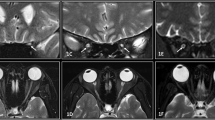

Subjective analysis of the optic nerves was limited to children without optic pathway glioma. Using T1-weighted 3-D MPRAGE sequences, transaxial and coronal images of the optic nerves were cropped so that the optic nerves were visualized from the orbital apex to the globe. These steps prevented the reviewer from discerning the NF1 diagnostic status of the subject. The subjective assessment of optic nerve tortuosity was performed by a pediatric neuroradiologist with 13 years of experience (R.C.M.). Scans were scored on a three-point scale: normal (0), intermediate tortuosity (1) and marked tortuosity (2) (Fig. 3). After the scans were scored, the images set was randomized and recoded with new scan IDs and a second subjective analysis was performed to assess test-retest reliability of the subjective interpretation. The retest analysis was completed with the same radiologist (RCM) and the same equipment 1 month after the original assessment.

Subject axial MRI scans. Subjective optic nerve tortuosity scores were determined by a radiologist (R.C.M.) on a three-point scale (from 0 to 2). a Optic nerve with a score of 0 (normal) in a 4-year-old girl. b Optic nerve with score of 1 (intermediate tortuosity) in a 2-year-old boy with NF1. c Optic nerve with a score of 2 (marked tortuosity) in a 5-year-old boy with NF1